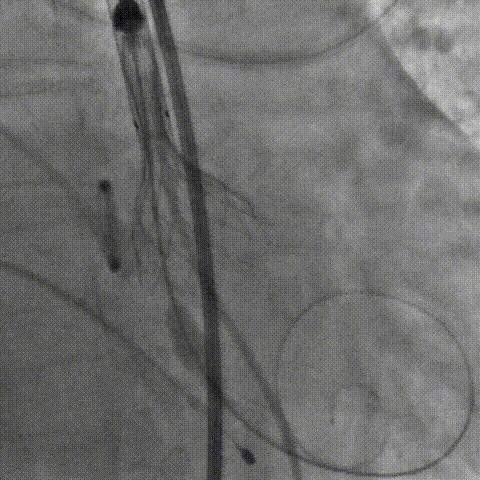

瓣膜成功释放

术后即刻超声显示:无主动脉瓣返流、无瓣周漏,PGmean:8mmHg,Vmax:2m/s,LVEF:58% 。

人工瓣膜释放后造影

术后,陶主任对TaurusElite™可回收输送器过弓性能和瓣膜释放稳定性给予了高度评价,对输送系统可通过6.2mm直径的股动脉也给予了肯定。